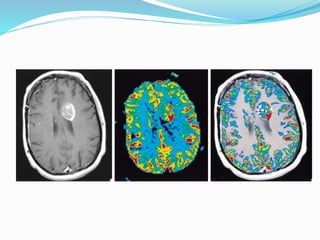

Brain tumors

DYNAMIC CONTRAST-ENHANCED

MRI

 malignant lesions usually show faster and higher levels

of enhancement than normal tissue. This

enhancement pattern of the malignant lesions reflects

increased vascularity (neoangiogenesis) and higher

endothelial permeability to the contrast molecules.

 dynamic contrast-enhanced MRI (DCE-MRI) is

modality of choice for the diagnosis and

characterization of the tumors of the brain, breast,

prostate, liver, cervix and musculoskeletal system